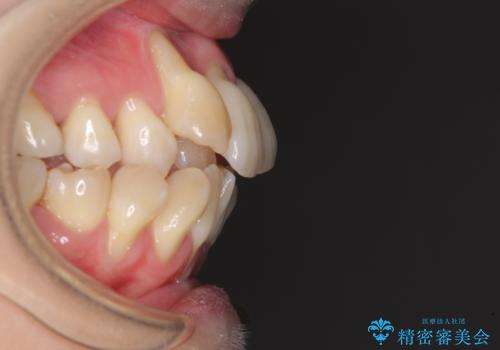

急速拡大装置 狭い骨幅を拡大した上で、顕著なデコボコを改善する抜歯矯正治療

- 前歯のデコボコと唇の閉じにくさを気にして来院された患者様です。

上顎骨よりも下顎骨の幅が広く、更には下顎骨が左側に変位していたため、より良い咬み合わせを達成することを目的として、急速拡大装置を用いて上顎骨を拡大することとしました。

デコボコが強い上に、口元の突出感も気にしていたため、上下左右の小臼歯4本を抜歯して、ワイヤー装置にて矯正治療を行うこととしました。

歯根露出が顕著であったため、歯の移動は早く、スムーズに治療を終えられるかと思いましたが、歯槽骨が硬く、治療は長期間に及びました。

過剰に力をかけ続ける事態となり、一部の歯では変色したり、神経が失活したりとトラブルが続きました。